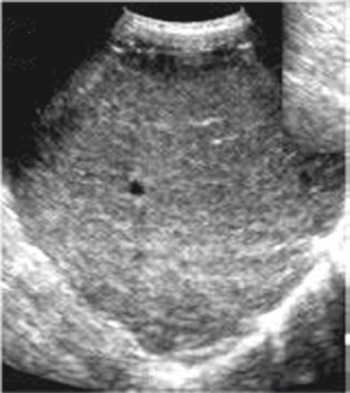

Иллюстрация к книге — Неалкогольная жировая болезнь печени [i_038.jpg]

Рис. 35. Эхограмма печени при НАЖБП

УЗИ имеет преимущества при скрининговой диагностике НАЖБП, особенно у пациентов без клинических симптомов поражения печени. При УЗИ печени определяется;

✓ диффузная гиперэхогенность паренхимы печени и неоднородность ее структуры;

✓ нечеткость и/или подчеркнутость сосудистого рисунка;

✓ дистальное затухание ЭХО-сигнала.